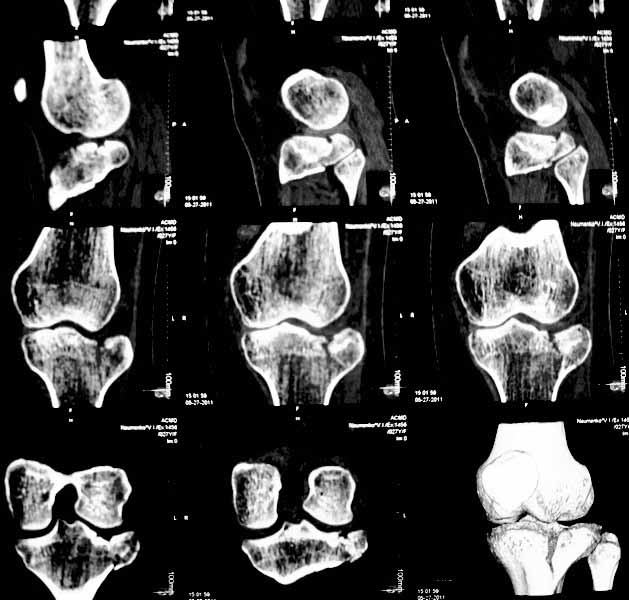

Застарелый перелом наружного мыщелка б.берцовой кости |

Уважаемые коллеги. Хочу представить вам клинический случай и получить информацию в отношении тактики лечения данной пациентки. Возраст 27 лет, парапланеристка, получила травму в Индии 28 апреля 2011г, упала с мотоцикла, получила боковой удар по левому коленному суставу. Первая помощь оказана в индийской клинике, установлен диагноз - Ссадины левого локтевого сустава, левого плеча, левой и правой стоп, повреждение связок левого коленного сустава (не указано каких). Со слов пациентки выполнены рентгеновские снимки голени (их не отдали). Наложена циркулярная рассеченная скотч-каст повязка без захвата стопы на левую ногу, рекомендовано консервативное лечение со сроком иммобилизации 6 недель. Пострадавшая оставалась в Индии и вернулась 17 мая.

26 мая обратилась ко мне за консультацией с вопросом – можно ли снять иммобилизацию немного раньше и начать ходить без костылей?. СКТ – снимки прилагаю.

-клинически – вальгизация коленного сустава, умеренная сглаженность контуров сустава, постиммобилизационная контрактура сустава, медиальной и латеральной нестабильности сустава нет.

Интересуют вопросы: -тактика лечения: -если операция, то стандартная открытая репозиция с приподнятием мениска, обзором части сустава, подъемом импактированного фрагмента, костной пластикой и фиксацией блокированной пластиной и винтами ( в больнице ЭОПа нет) или есть другие варианты? -понимаю, что операция сложна, идеала достичь будет также сложно, но возможно ли за сустав побороться именно сейчас?, а не ждать ЛФК, реабилитации, получения результатов консервативного лечения и дальнейших артроскопий, остеотомий и пр. -какие результаты лечения можно предположительно получить после выполнения операции с улучшенным, но неидеальным сопоставлением отломков и какие результаты можно ожидать от консервативной методики, будет ли лучше? -если тактика лечения консервативная, то какие ориентировочные сроки осевой нагрузки на больную ногу, сроки перехода на трость. Буду рад выслушать все предложения. Заранее благодарен. С уважением Голиков Валерий, БСМП, Киев

Восстановление суставной поверхности,поднять нар.мыщелок,вложить аутотрасплантат из крыла подвздошной кости ,стабильная фиксация,ранняя мобилизация,поздняя нагрузка- через 3 мес.Какая медицинская страховка, была у пациентки?